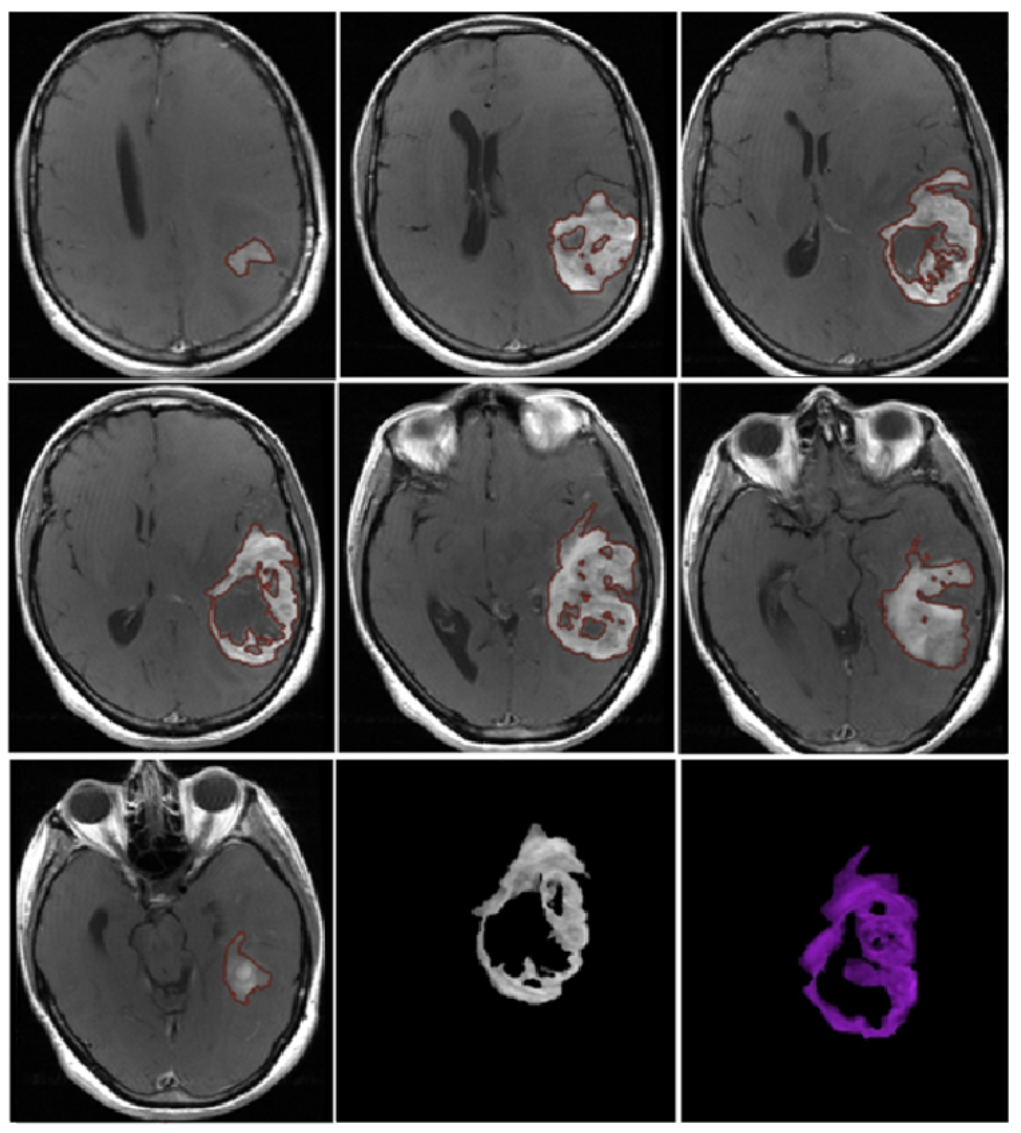

- Morphological appearance: We divided GB lesions into three categories based on the enhancing wall thickness: thin, <3 mm; thin-nodular, when the enhancing wall showed focal thickenings > 3 mm; and nodular, when solid appearance was predominant and intratumoral necrosis was absent or <1.5 cm3. A total of 11 (13%) masses showed a thin pattern, 51 (58%) showed a thin-nodular pattern, and 25 (29%) showed a nodular pattern.

3.2. Quantitative Analysis